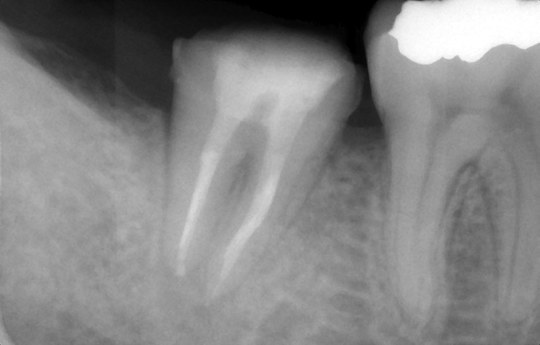

根の先の骨まで感染 骨が溶けている状態

数回の根管治療・根管充填の直後

根管治療終了から3か月 骨が回復傾向

かぶせものをして1年6か月

完全に骨は回復

また、根管(歯根の中にある管)からその周囲の骨に、虫歯由来の細菌が感染すると免疫反応により炎症を起こし骨が溶けます。これを根尖病巣と呼びます。根尖病巣は一種の歯周病であり、痛みが出にくいため放置されることが非常に多いです。そのままにしておくと、根の先の骨が大きく溶けつづけ、抜歯に至ることになります。

それを防ぐためには、感染源である根管の細菌を取り除き感染を止めることで、骨が再生する環境を作ってあげる必要があります。それが根管治療の目的となります。

その環境ができたら速やかに、しっかりと消毒をしたうえで根管を密に充填いたします。最終の土台やかぶせものの隙間から細菌が侵入しても密な根管充填が細菌の再侵入を遅らせてくれます。